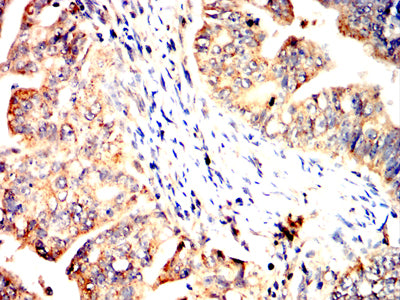

分类: 科研抗体货号: 32337别名: BYK; Dtk; RSE; Rek; Sky; Tif; Etk-2应用: IHC,FCM反应种属: Human

分类: 科研抗体货号: 32350别名: K14; NFJ; CK14; EBS1; EBS3; EBS4; EBS1A; EBS1B; EBS1C; EBS1D应用: WB,IHC,IF,FCM反应种属: Human

分类: 科研抗体货号: 32340别名: A4; STV1; VPH1; VPP2; DRTA3; RTA1C; RTADR; ATP6N2; RDRTA2; ATP6N1B应用: IHC,FCM反应种属: Human

分类: 科研抗体货号: 32349别名: CL2; DCK2; CLIK2; DCDC3; CLICK2; DCDC3B; DCAMKL2; CLICK-II应用: IHC,FCM反应种属: Human

分类: 科研抗体货号: 32334别名: GLUT14; SLC2A3P3应用: IHC,IF反应种属: Human

分类: 科研抗体货号: 32339别名: AOM; ANFH; SEDC; STL1; COL11A3应用: IHC,FCM反应种属: Human

分类: 科研抗体货号: 32333别名: TLT2; TLT-2; C6orf76; dJ238O23.1应用: IHC,IF,FCM反应种属: Human